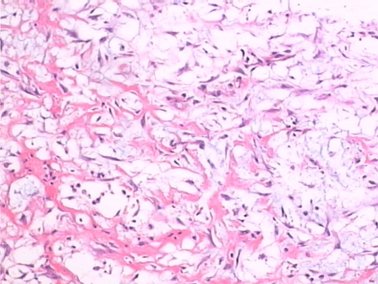

瘤细胞分化程度不一,细胞大部分轻度异型性,少部分呈中度异型性,核增大、深染,可见核分裂像(2-3个/10HPF)。间质可见胶原纤维,并局灶玻璃样变性,肿瘤细胞间有较多薄壁毛细血管,淋巴细胞和浆细胞浸润不明显,如下图4。

图4 HE×100